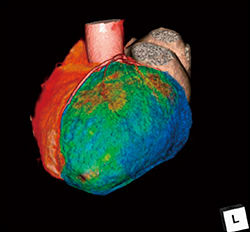

“CT心筋血流解析”は,Stress/Restの1フェーズの心臓CTデータを使用して,左室心筋血流のTPRをそれぞれ,もしくは同時に解析するソフトウェアである。左室心筋と冠動脈を自動抽出し,解析結果をフュージョン表示し,右側にはBull’s Eye Mapを表示する(図2)。17セグメント表示にも対応し,虚血エリアの把握が容易になっている。

図2 CT心筋血流解析の解析画面